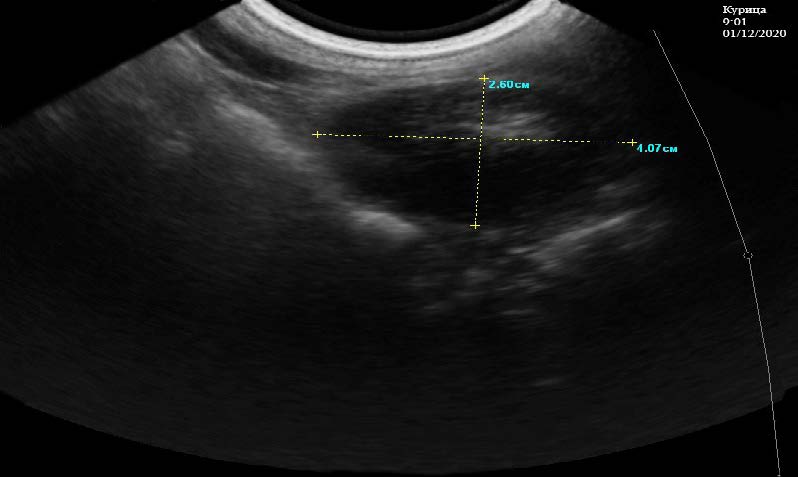

Четвертый этап исследования проводили в 9:01 часов 01.12.2020 г. Яйцо, находилось в матке в течение 20 часов, за это время произошла минерализация и покрытие его скорлупой. В матке яйцевода на эхограмме визуализируются анэхогенное образование – яйцо размером 4,70*2,60 см. В центре него выявляется гипоэхогенная структура с нечеткими контурами – желток. Контуры яйца ровные, границы нечеткие. Яйцо полностью заполняет полость матки, просвет между яйцом и стенкой матки отсутствует, контуры стенок матки четкие и ровные с однородной эхогенной структурой, узловых образований не обнаружено, сосуды матки не расширены. По его периферии видна тонкая гипоэхогенная линия – скорлупа. Дистально визуализируется слабый артефакт (рис. 5).

Рис. 5. Полость матки яйцевода у курицы кросс «Хайсекс белый» заполненная яйцом. 9:01 ч. 01.12.2020 г.